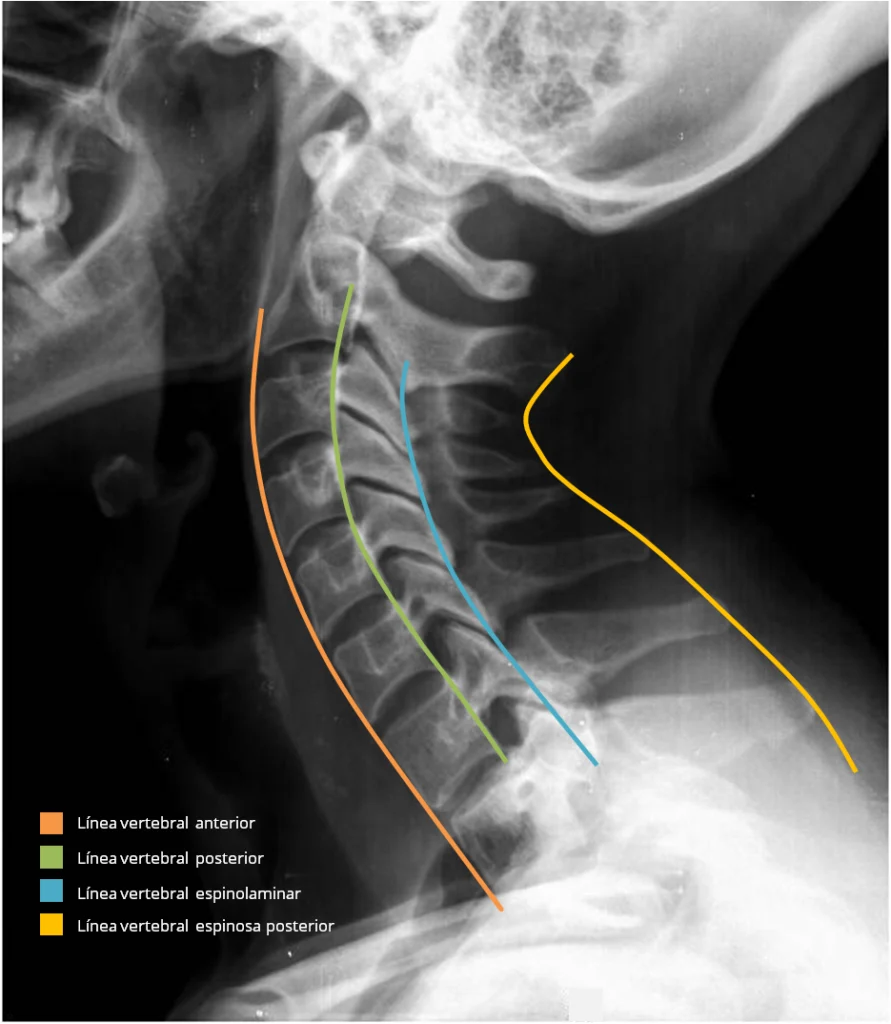

Radiografía de columna cervical lateral – Las 4 líneas. Desde el margen anterior al posterior tenemos:

- La línea vertebral anterior, (naranja) recorre el borde anterior de los cuerpos vertebrales.

- La línea vertebral posterior, (verde) recorre el borde posterior de los cuerpos vertebrales.

- La línea espinolaminar, (azul) recorre el borde anterior del arco posterior.

- La línea espinosa posterior, (amarillo) une el vértice de las apófisis espinosas.

En la imagen vemos una radiografía de columna cervical lateral donde he trazado las 4 líneas. Desde el margen anterior al posterior tenemos: